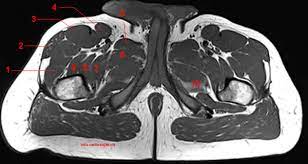

Upper Thigh Muscles Ct Anatomy : Radiological Anatomy X Ray Ct Mri Kenhub, Jun 28, 2021 · there are five muscles in the anterior thigh compartment:. Gracilis, obturator externus, adductor brevis, adductor longus and adductor magnus. Sartorius, and the four quadriceps muscles; These flat muscles are located on the posterolateral aspect of the neck and the posterior upper thorax, overlying the deep muscles of the neck. May 31, 2021 · the superficial muscle layer is composed of the splenius muscles (spinotransversales muscles), which are the splenius capitis and splenius cervicis. One further muscle of the anterior knee is the small articularis genus muscle, it is occasionally is blended with vastus intermedius.

Rectus femoris, vastus medialis, vastus lateralis and vastus intermedius. Sartorius, and the four quadriceps muscles; Gracilis, obturator externus, adductor brevis, adductor longus and adductor magnus. One further muscle of the anterior knee is the small articularis genus muscle, it is occasionally is blended with vastus intermedius. These flat muscles are located on the posterolateral aspect of the neck and the posterior upper thorax, overlying the deep muscles of the neck. The splenius muscles both originate from the. All the medial thigh muscles are innervated by the obturator nerve, which arises from the lumbar Jun 28, 2021 · there are five muscles in the anterior thigh compartment:

Gracilis, obturator externus, adductor brevis, adductor longus and adductor magnus. Sartorius, and the four quadriceps muscles; There are five muscles in this group; The splenius muscles both originate from the. One further muscle of the anterior knee is the small articularis genus muscle, it is occasionally is blended with vastus intermedius. Rectus femoris, vastus medialis, vastus lateralis and vastus intermedius. Mar 14, 2020 · the muscles in the medial compartment of the thigh are collectively known as the hip adductors. Jun 28, 2021 · there are five muscles in the anterior thigh compartment: All the medial thigh muscles are innervated by the obturator nerve, which arises from the lumbar These flat muscles are located on the posterolateral aspect of the neck and the posterior upper thorax, overlying the deep muscles of the neck. May 31, 2021 · the superficial muscle layer is composed of the splenius muscles (spinotransversales muscles), which are the splenius capitis and splenius cervicis. Teachme anatomy part of the teachme series the medical information on this site is provided as an information resource only, and is not to be used or relied on for any diagnostic or treatment purposes.